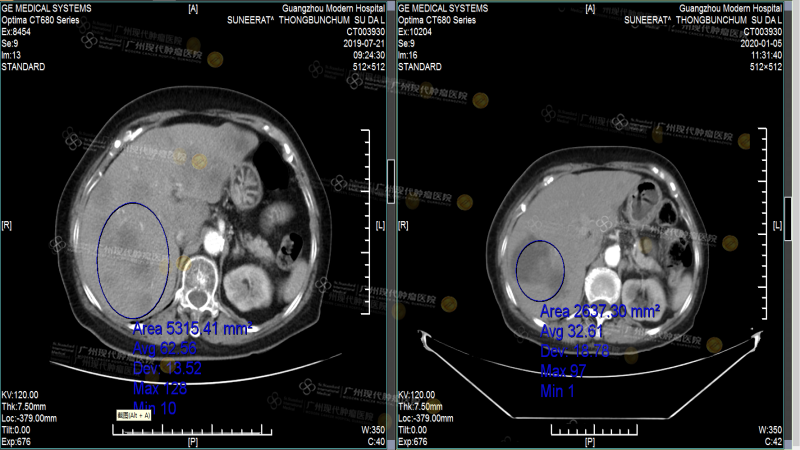

Sau khi nhập viện, bác sĩ đã thực hiện một loạt các xét nghiệm, tôi nhớ rất rõ quá trình kiểm tra, vì nó rất tỉ mỉ. So với các xét nghiệm tôi làm ở Thái Lan, bác sĩ ở đây hỏi rất kỹ và giải thích báo cáo kết quả rất rõ ràng. Sau khi có kết quả xét nghiệm, bác sĩ phát hiện các tế bào ung thư đã di căn sang gan, đồng thời xác nhận tôi bị ung thư vú tái phát sau phẫu thuật với di căn gan giai đoạn IV. Vì khối u quá lớn và số lượng quá nhiều, cùng với các bệnh nền như huyết áp cao cấp độ 3 và tiểu đường type 2, nhóm đa ngành MDT tại Bệnh viện Ung bướu St.Stamford Quảng Châu, dựa trên tiến triển bệnh lý và thể trạng của tôi, đã chọn phương pháp Vi sóng để tiêu diệt và giảm kích thước khối u gan. Phương pháp này sử dụng kim vi sóng để xuyên qua khối u vú và làm chúng hoại tử mà không cần phẫu thuật. Quá trình này rất ít đau đớn, phù hợp với tôi là một bệnh nhân cao tuổi. Sau khi khối u giảm kích thước, các bác sĩ tiếp tục kết hợp với điều trị can thiệp, dùng thuốc điều trị và thuyên tắc mạch cho khối u vú. So với hóa trị truyền thống, phương pháp này có nồng độ thuốc cao và không làm tổn thương các mô lành, rất phù hợp với thể trạng yếu ớt của tôi. Sau một loạt các liệu pháp điều trị này, các khối u của tôi đã giảm kích thước đáng kể và hoàn toàn đạt tiêu chuẩn sống cùng với khối u.